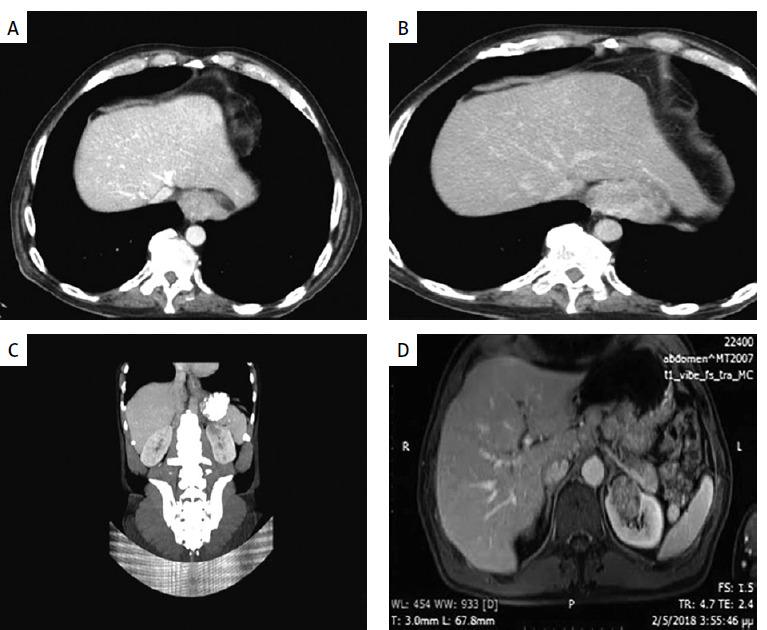

Abstract Image